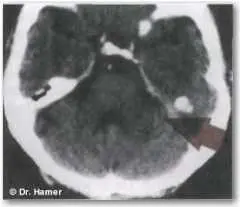

Примерна данном снимке виден НН в ПКЛфазе А соответствующий опухоли легких - фото 14

Пример:на данном снимке виден НН в ПКЛ-фазе А, соответствующий опухоли легких, указывающий на разрешённый «конфликт страха смерти». Большинство подобных «конфликтов страха смерти», приводящих к раку легких, вызываются постановкой неблагоприятного диагноза с негативным прогнозом.